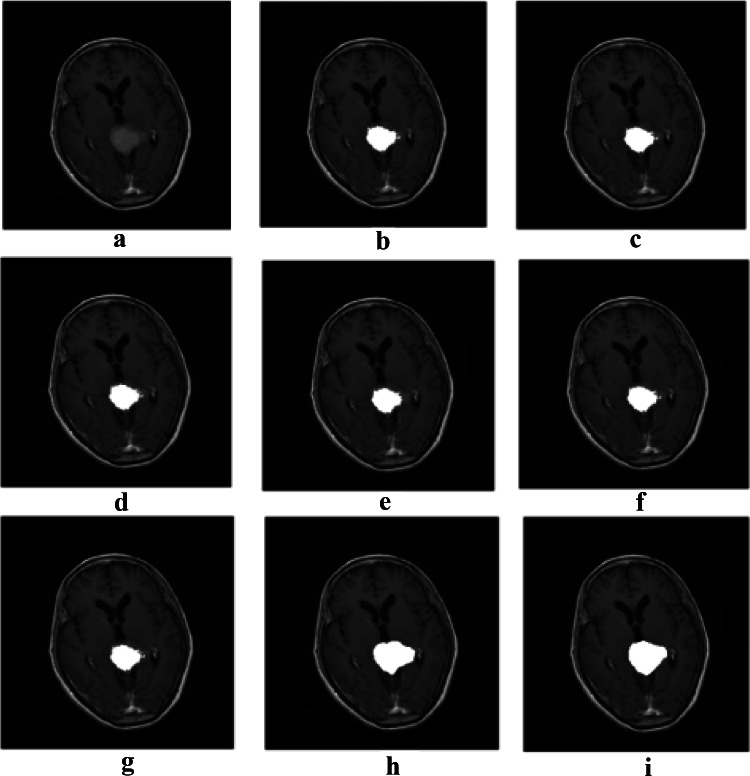

After comparing the results of the mentioned algorithms and evaluating the defined comparison criteria, the PSO algorithm had the best performance among the other algorithms. Nevertheless, to achieve a higher accuracy, it is required to use an algorithm which is able to obtain the edges of the tumor more accurately. The Active contour algorithm can perform very well but it is highly dependent on the initial boundary. Henceforth, the tumor area detected by the PSO algorithm is used as an initial boundary for the Active contour model. Figure 5 shows the results of tumor detection from a MRI brain image using Active contour with an initial boundary obtained by PSO algorithm for both types of tumors. We call this combination as our proposed algorithm. Rows 1 to 3 in Fig. 5 depict the images containing the pituitary tumor, and rows 4 to 6 show the images containing the Meningioma tumor. The results of PSO algorithm and our proposed algorithm for 30 images containing the Meningioma tumor are presented in Table 8. All the evaluation criteria computed for the proposed algorithm, except Precision, have been significantly increased, which shows that the proposed algorithm has a higher ability to obtain tumor edges than the PSO. The high Precision of PSO algorithm is due to the fact that the algorithm has obtained the area inside the tumor, so it has a low FP, and as a result, the Precision has been increased according to its formula. However, since this algorithm has performed poorly in obtaining the edges, the FN is very high which results in a very low Recall and other evaluation criteria. Figure 6 shows the results of tumor detection on MRI brain images containing the Meningioma tumor using different algorithms. Figure 7 shows the same results on MRI brain images containing the Pituitary tumor.

Fig. 5.

Tumor detection results for both types of tumors: a original images, b initial segmentation using PSO algorithm, c tumor area by means of PSO, d the proposed algorithm, and e ground truth

Fig. 6.

Results of tumor detection on a MRI brain image containing the Meningioma tumor: a original image, b ABC, c DE, d GA, e HS, f GWO, g PSO, h) the proposed algorithm, and i ground truth